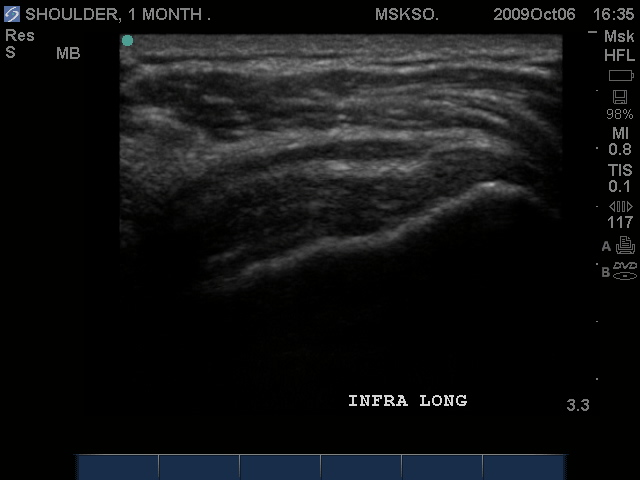

Long axis image of the Infraspinatus tendon over the posterior Greater Tuberosity also confirms bursal enlargement.

Compression shows this is not simple bursal fluid.